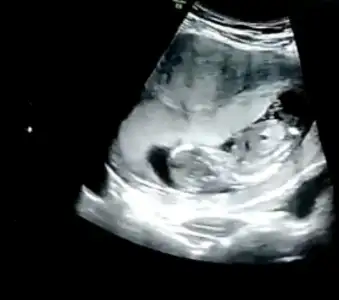

Ikra meyra Ikra meyra 11+1 de atmıştım size erkek sanki demiştiniz bu 12+2 foto tahmin ederseniz çok sevinirim

• IMG20210319145719.webp

IMG20210319145719.webp

39,1 KB · Görüntüleme: 95